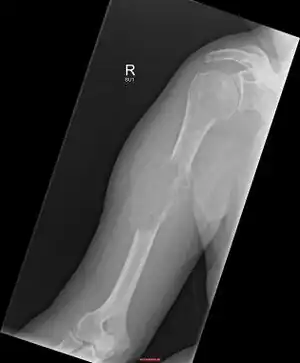

| Solitary plasmacytoma in the long bone of the upper arm | |

1.a. X-ray: solitary plasmacytoma upper arm near shoulder